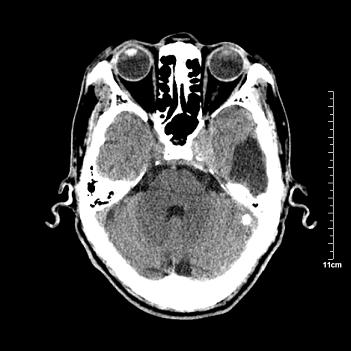

男性患者,72岁,近两天头晕来我院就诊。 因患者血压太高而未做增强,建议病人去市医院做mri检查。等得到mri随访结果再公布给大家。 测及左颞顶枕叶病灶ct值分别为5hu 30hu 729hu。

考虑左侧颞顶枕叶少突胶质细胞瘤。 今天随访患者手术病理结果 病理回报为胶质瘤2级 钙化

左侧颞顶枕叶巨大囊性病灶,灶内见小片实性区且灶内及灶周围大量团块状钙化影,灶周水肿少.左侧室枕角内见环形钙化,可见较清晰前壁,钙化与室壁似有间隙.

考虑1寄生虫病2表皮样囊肿钙化3血管畸形,其他不排

囊变明显,钙化明显,部分实性组织,轻度占位,左侧脑室受压---考虑 少突胶质细胞瘤,畸胎瘤,寄生虫病